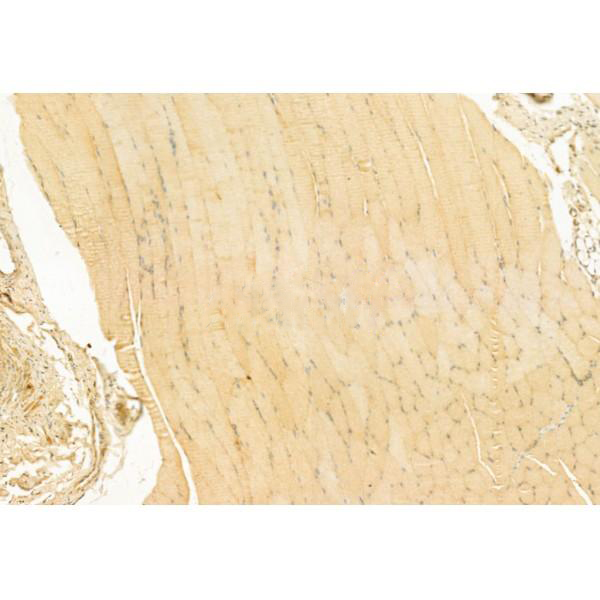

ab11649 at 1/100 staining Rat muscle tissue by IHC-P. The sample was formaldehyde fixed and a heat mediated antigen retrieval step in citrate buffer was performed. The sample was then blocked and incubated with the primary antibody at 4°C overnight. An HRP conjugated anti-Rabbit antibody was used as the secondary antibody....